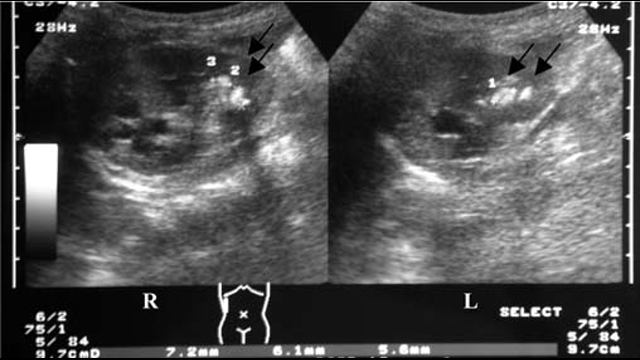

Multiple-bilateral-renal-calculi and medullary-nephrocalcinosis